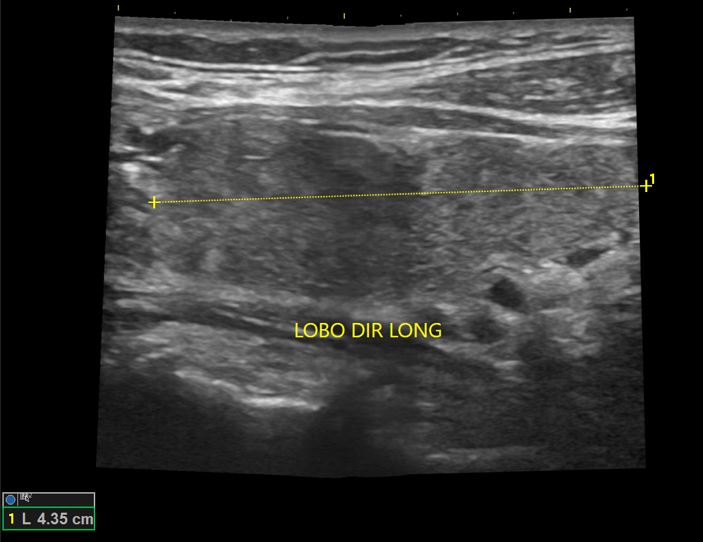

Nódulos de Tireoide

USG de nódulos benignos